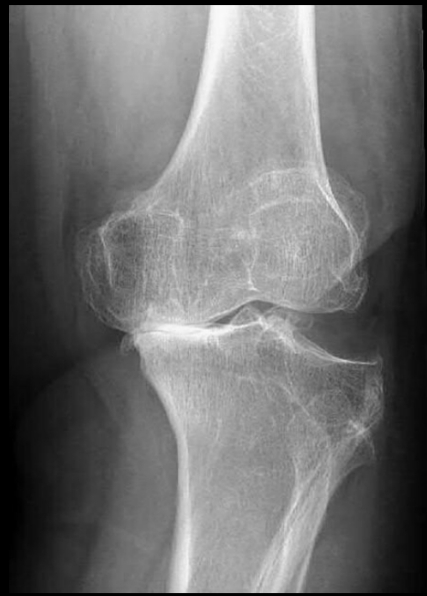

18

Q

Método más usado para ver la gonartrosis

A

Rx.

Se ven los datos de artrosis:

- Osteofitos

- Disminución del espacio

- Esclerosis ósea

- Quistes subcondrales

- Deformidad ósea

En TC se ve lo mismo